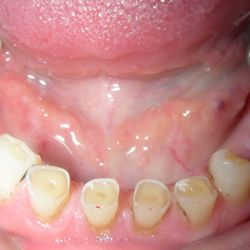

Ο ασθενής αυτός ήταν έντονα δυσαρεστημένος με την εμφάνιση των άνω και κάτω δοντιών του. Τα δοντια του ηταν σε τερματικό στάδιο και η μάσηση ήταν σχεδόν αδύνατη.

Με την χρήση οδοντικών εμφυτευμάτων καταφέραμε να αποκαταστήσουμε το στόμα του.

Οι νέες μεταλλοκεραμικές γέφυρες που κατασκευάστηκαν, αποκατέστησαν την αισθητική ισορροπία του χαμόγελου, την σωστή μάσηση και επανέφεραν την αυτοπεποίθηση του ασθενούς.